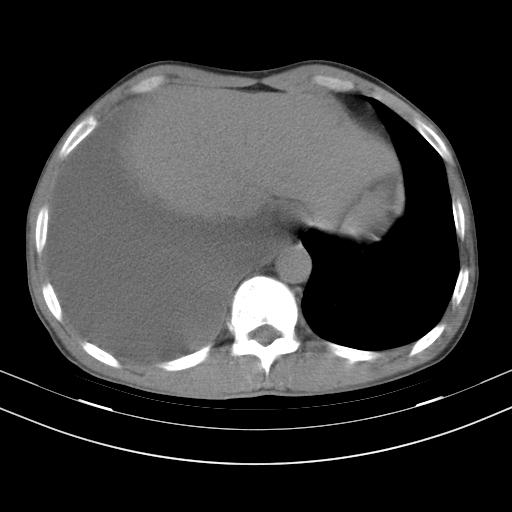

男性,44岁,结核病史多年。现胸闷气短,咳嗽,偶咳血。

右侧胸腔积液

右肺下叶不张

双肺多发结节影最分空洞形成考虑占位不除外结核

双肺陈旧性病变

1、右侧大量胸腔积液伴右肺压缩性膨胀不全,建议抽液治疗后复查 2、两肺继发性tb伴空洞形成。

1)两肺继发性肺结核伴空洞形成,左肺多发性结核球。2)右侧大量胸腔积液伴右肺部分膨胀不全。3)纵隔淋巴结肿大。

吉大一院胸水抽检结果:结核性胸水